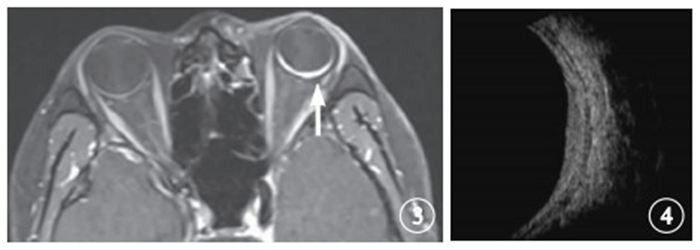

圖1

治療前左眼增強MRI像。可見脈絡膜血管瘤(白箭)及視網膜脫離(白箭頭) ? ?圖 2 治療前左眼B型超聲像。可見脈絡膜血管瘤,腫瘤體積為5.35 cm3

圖1

治療前左眼增強MRI像。可見脈絡膜血管瘤(白箭)及視網膜脫離(白箭頭) ? ?圖 2 治療前左眼B型超聲像。可見脈絡膜血管瘤,腫瘤體積為5.35 cm3

圖1

治療前左眼增強MRI像。可見脈絡膜血管瘤(白箭)及視網膜脫離(白箭頭) ? ?圖 2 治療前左眼B型超聲像。可見脈絡膜血管瘤,腫瘤體積為5.35 cm3

圖1

治療前左眼增強MRI像。可見脈絡膜血管瘤(白箭)及視網膜脫離(白箭頭) ? ?圖 2 治療前左眼B型超聲像。可見脈絡膜血管瘤,腫瘤體積為5.35 cm3